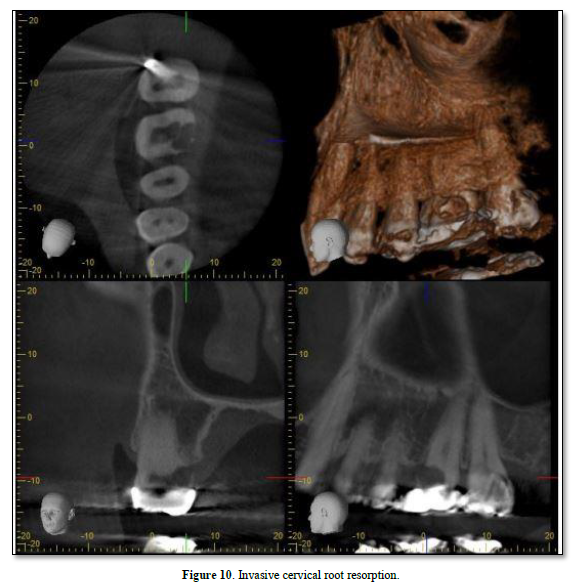

Cervical RR, a relatively uncommon form of external RR, is characterized by its invasive nature and can be detected by CBCT [58]. It tends to discolor the tooth crown giving it a pink hue (Figure 10) [53]. The exact cause of invasive cervical resorption is unknown; however, there is a strong correlation between orthodontic treatment, trauma, and intracoronal bleaching [59]. This type of resorption occurs below the epithelial attachments of the tooth [48]. As the source of infection is not the pulp, it has been suggested that bacteria in the sulcus stimulate and sustain inflammatory responses in the periodontium [60]. The destruction will continue until either there is no root structure left, or the inflammatory stimulus is removed by intervention [49]. Heithersay [61] has classified this type of resorption into four classes of severity with the proposed treatment regimens. Treatment may involve vital pulp therapy [62]; root canal treatment [42]; or surgical management [63], which may include topical trichloroacetic acid application, curettage, bioactive materials (e.g., MTA, Biodentine etc.) [64], and restoration with glass ionomer cement as needed [59].